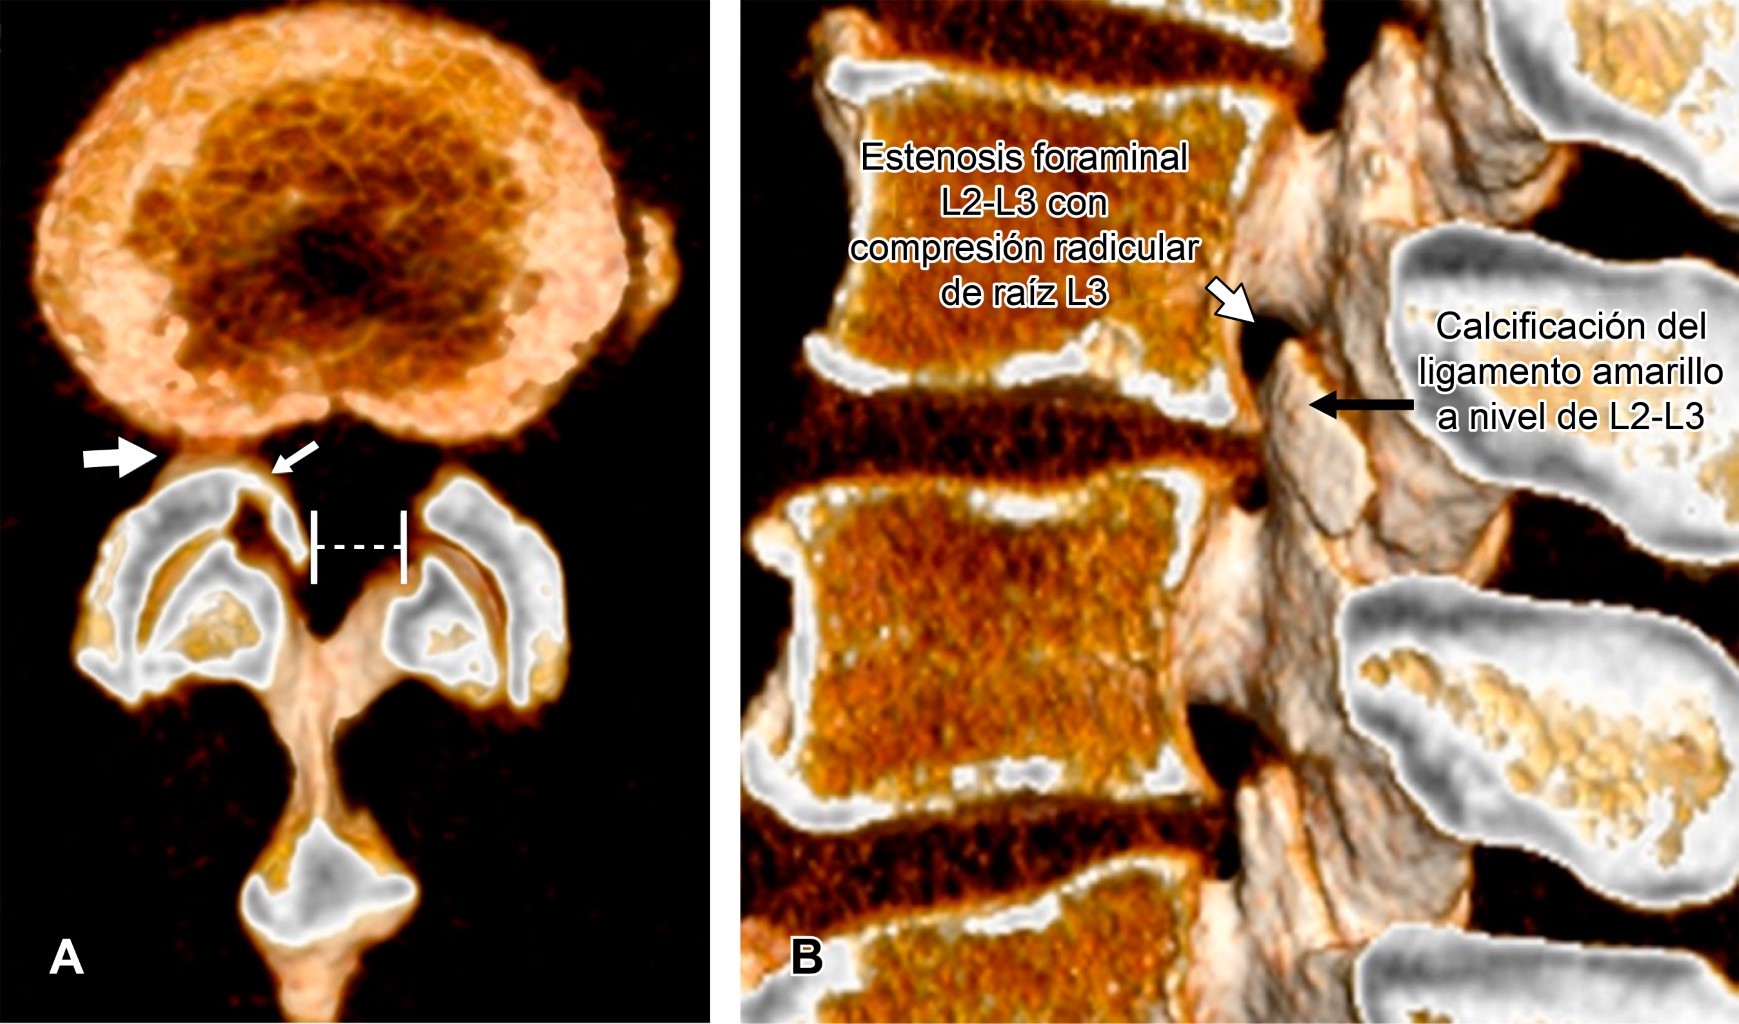

Masculino de 58 años, estibador de pieles (con peso de 40 kg) en los últimos 30 años (cargando los rollos de piel sobre hombro derecho), acude a rehabilitación derivado por medicina general debido a: dolor lumbar de cinco años de evolución con calificación 5/10 en escala visual analógica (EVA), con exacerbaciones dos a tres veces/año que mejoran con reposo de 24 horas y analgésico. La última crisis de dolor lumbar con calificación 9/10 en EVA inició un mes atrás, agregándose irradiación a cara anterior de muslo derecho, correspondiendo a dermatoma L3 que se exacerba con la ambulación y extensión de columna que mejora en decúbito lateral derecho y con la flexión de extremidades pélvicas. La tomografía de columna lumbar mostró: estenosis del canal lumbar y estenosis foraminal L2-L3 derecha, condicionada por artrosis facetaria y calcificación del ligamento amarillo ipsilateral (Figura 1). El paciente fue derivado a neurocirugía para valoración quirúrgica. La estenosis espinal degenerativa del canal lumbar es el estrechamiento del canal vertebral, del receso lateral o de los agujeros de conjunción; secundario a hipertrofia degenerativa y progresiva de cualquiera de las estructuras óseas, cartilaginosas o ligamentosas que culmina en una compresión neurológica.

Figura 1